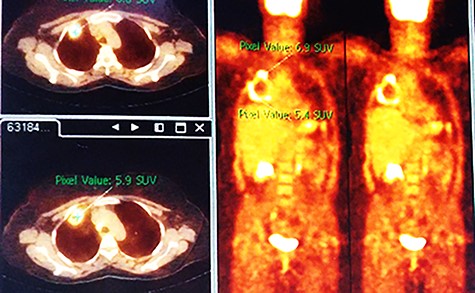

Chest X-ray (CXR) showed a heterogeneous density with irregular margins in the right lung (Fig. 1). CT scan demonstrated a heterogeneous mass that measured 5.5 × 6 × 7.8 cm with irregular thick margins. The mass was anteriorly located in the upper lobe of the right lung with air bubbles and necrosis (Fig. 2). Two lymphadenopathies were observed that measured around 2 cm each; one of which was in the hilum of the right lung and the other was located inferior to the right main bronchus. No other lesion was detected elsewhere. PET scan was also suggestive of malignancy as it demonstrated a heterogeneous mass with irregular margins which had irregular enhancement in the peripheral, suggesting hyper metabolic retention. The standardized uptake values (SUV) of the mass ranged between 4 and 7 with central necrosis and multiple gas bubbles. Multiple lymphadenopathies were also observed with different sizes ranged from 10 to 20 mm with SUVmax reaching 7 (Fig. 3). Bronchoscopy found an erythematous and oedematous opening of the anterior segment of the right upper lobe of the lung and epithelial dysplasia was found with bronchial lavage (BAL), but endobrachial biopsy was not conclusive.